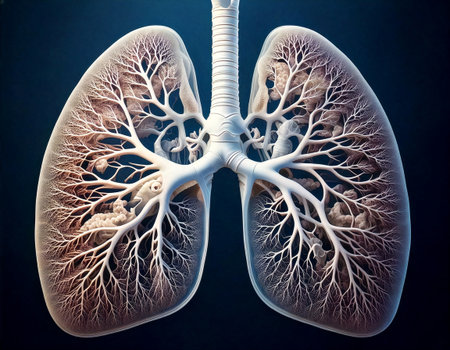

Lungs of human, 3D illustration. The structure of the human lungs.

This detailed illustration presents human lungs, showing their unique bronchi and alveoli structures. It serves as a visual aid for understanding the respiratory system.

An artistic visualization features a pair of human lungs, with elaborate branching structures resembling trees. This imaginative depiction highlights the intricately anatomical details and textures